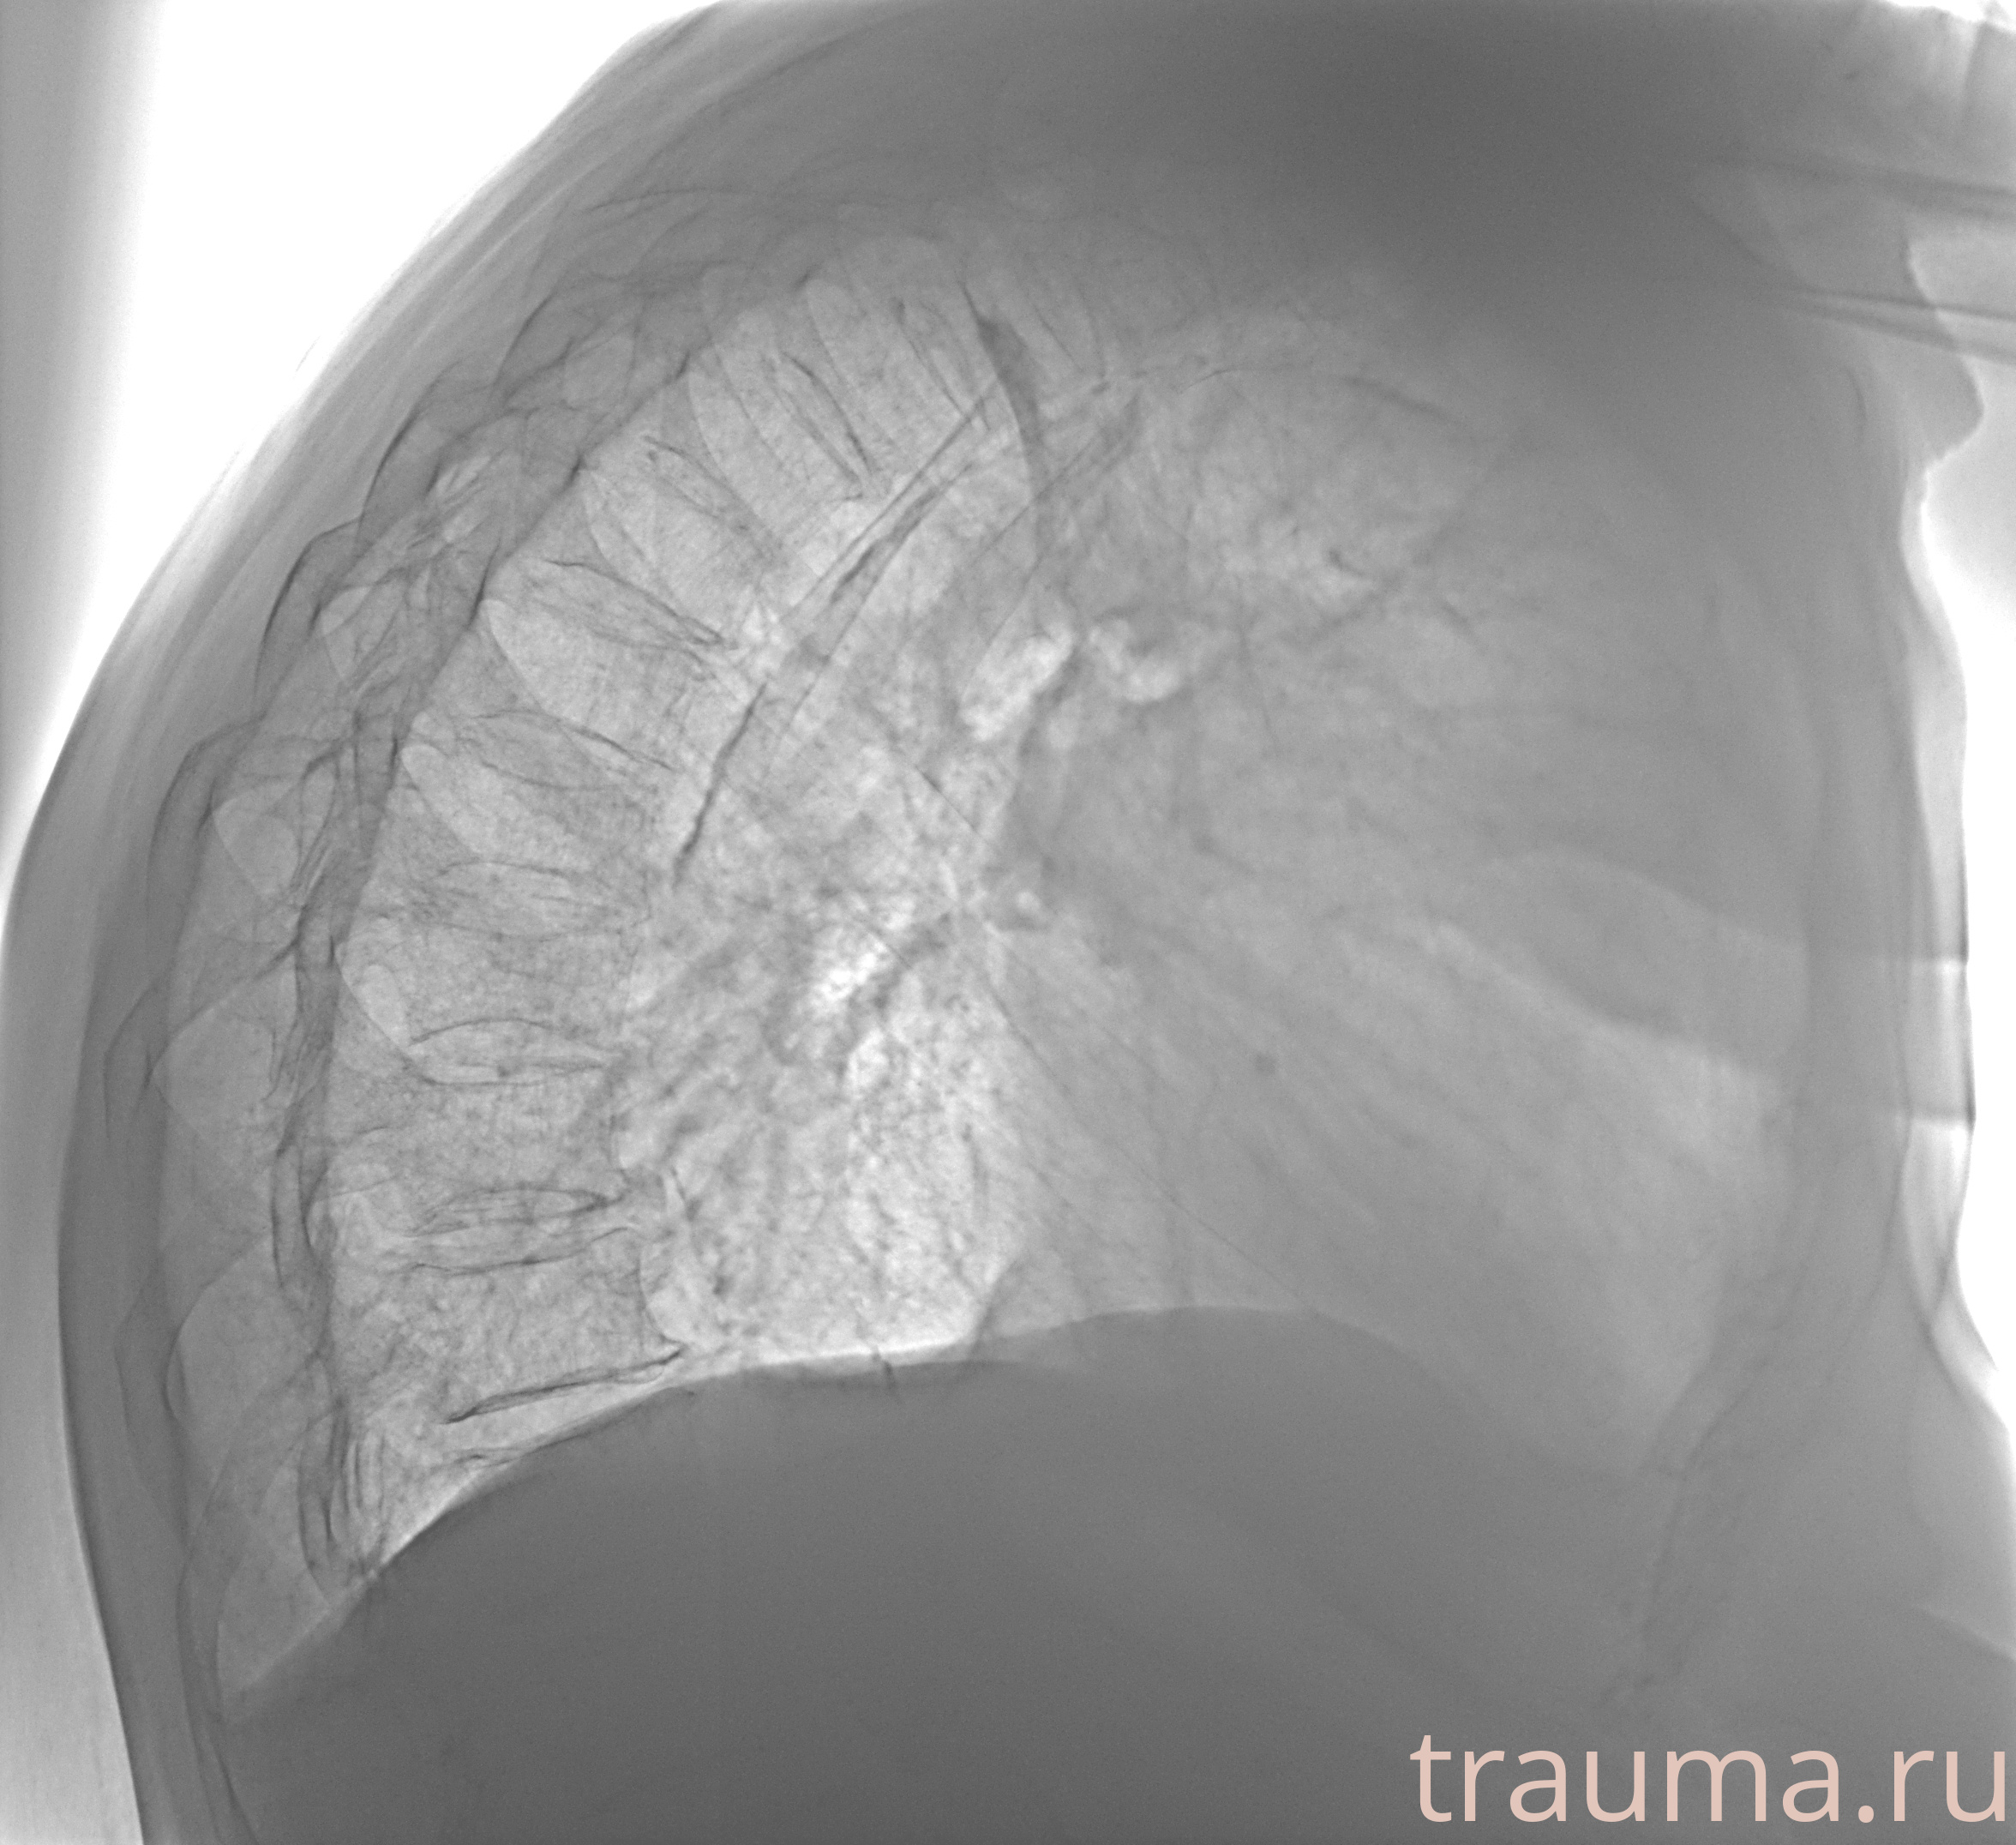

Рентген на дому: по вашему адресу приезжает врач-рентгенолог, травматолог-ортопед с мобильным рентгеновским аппаратом, проводит диагностику травмы или заболевания, делает необходимые рентгенограммы, дает рекомендации по дальнейшему лечению. Получить качественные снимки в домашних условиях возможно благодаря уникальной методике, разработанной МосРентген Центром для института  Склифосовского